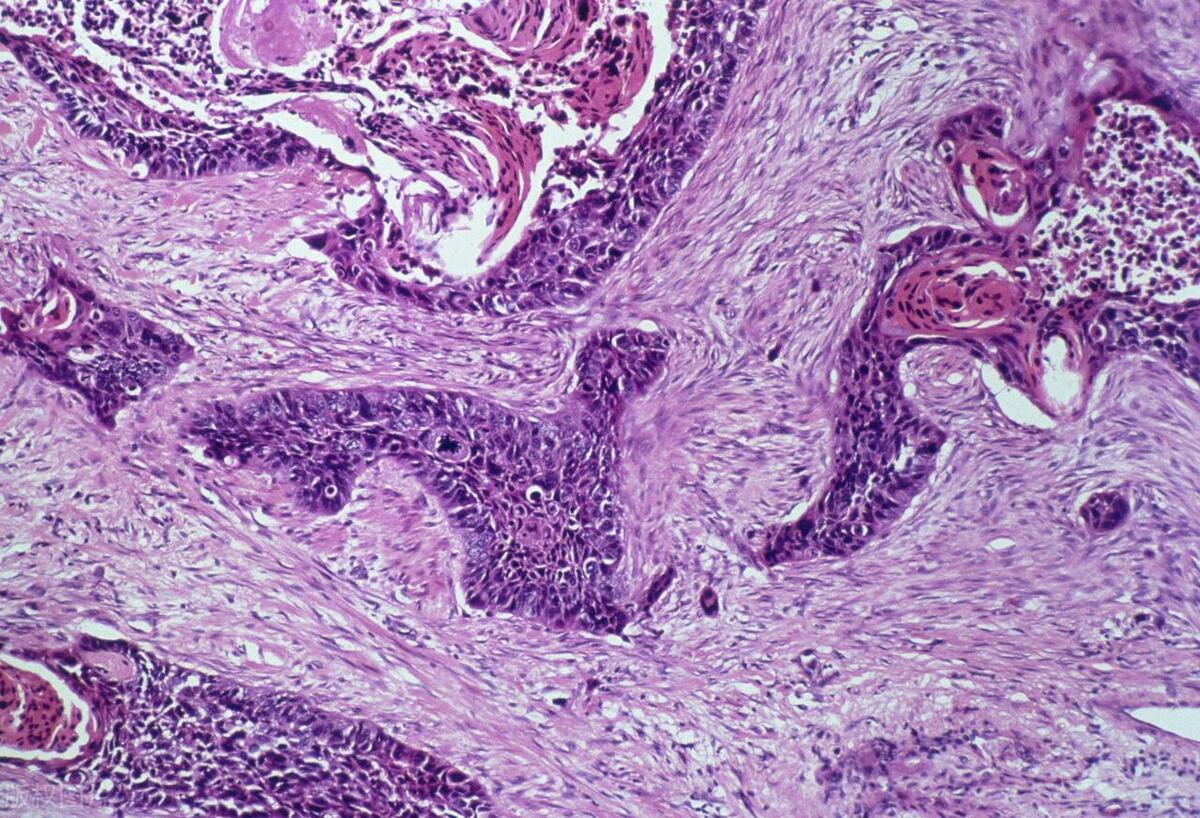

冰冻切片快速病理技术是一种在低温环境下快速冷冻组织样本并进行切片的诊断方法。 这项技术最早由Pieter de Riemer于1818年发明,并在1891年由Halsted和Accarty正式列为诊断方法。经过近两个世纪的发展,冰冻切片技术已成为临床病理诊断中不可或缺的重要手段。

与传统的石蜡切片相比,冰冻切片技术具有操作简便、诊断快速等显著优势。 石蜡切片虽然能较好地保存组织结构,适合长期保存,但在制片过程中需要经过酒精、二甲苯等有机溶剂处理,这会导致组织内抗原活性大量丢失。而冰冻切片则能较好地保存多种抗原的免疫活性,尤其是细胞表面抗原。然而, 冰冻切片也存在组织易碎、完整切片结构较难获取等缺点。